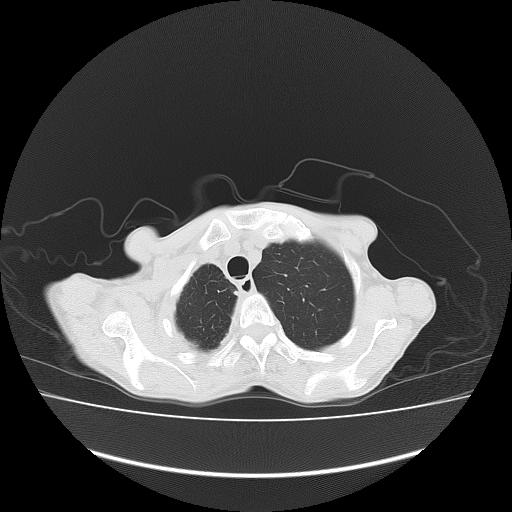

标题: CT16930:女 59 胸痛6个月 胸水脱落细胞学见瘤细胞 [打印本页]

标题: CT16930:女 59 胸痛6个月 胸水脱落细胞学见瘤细胞

右侧胸膜增厚,局部呈结节状增厚,右侧胸腔少量积液。双肺未见确切肿块影。纵隔未见淋巴结肿大。气管、支气管通畅。考虑右侧胸膜间皮瘤(恶性?)可能性大。不除外癌性胸膜炎。

右侧广泛胸膜增厚,局部呈结节状增厚,右侧胸腔少量积液。双肺未见确切肿块影。纵隔未见淋巴结肿大。气管、支气管通畅。考虑右侧胸膜间皮瘤(恶性?)可能性大。支持!